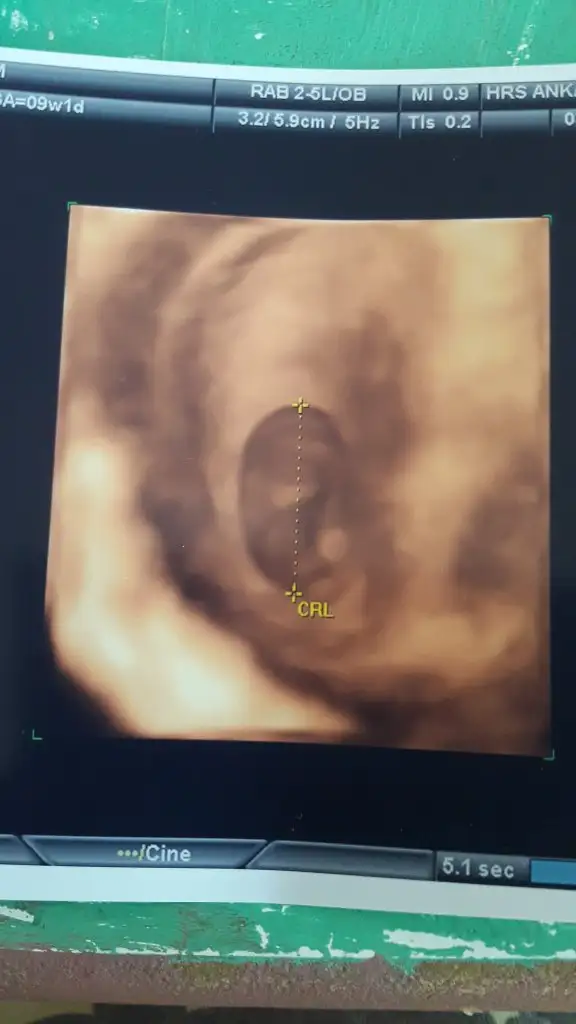

Kızlar iyiymiş şükür plesenta önde hematom oluşmuş ileriki haftalarda düzelir dedi dinlen ağır iş yapma su iç dedi.. sonuçlarım da iyiymiş. Darısı diğer haber bekleyenlere

Her şeyin yolunda olmasına sevindim canım. gelecek haftalarda düzelecek dediği için hemotoma da takılmamak lazım.. belirtiler ortaya çıkıp, kaybolabiliyor sonuçta çok kendini dinlemeden hamileliğin tadını çıkarmak en güzeli.. bir sonraki kontrol ne zaman ?Kızlar iyiymiş şükür plesenta önde hematom oluşmuş ileriki haftalarda düzelir dedi dinlen ağır iş yapma su iç dedi.. sonuçlarım da iyiymiş. Darısı diğer haber bekleyenlere

Sağol kuzum çok sağol.. ayy inşallah düzeliyor her şey yolunda amiiinn❤ 24üne verdi %70 tahmin yapabiliriz dedi.Her şeyin yolunda olmasına sevindim canım. gelecek haftalarda düzelecek dediği için hemotoma da takılmamak lazım.. belirtiler ortaya çıkıp, kaybolabiliyor sonuçta çok kendini dinlemeden hamileliğin tadını çıkarmak en güzeli.. bir sonraki kontrol ne zaman ?